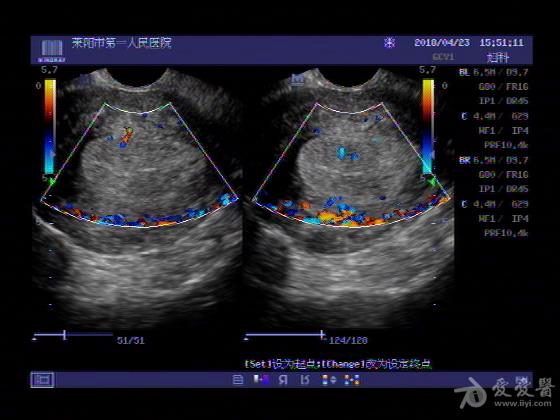

女,48岁,月经量多,两个月,一年前出现过类似现象,刮宫吃药后缓解。

超声可见:子宫内膜显著增厚,后肌壁内膜可见范围约3.27X0.90CM低回声区,CDFI显示较丰富线样血流,宫底宫腔内见类**状低回声结节。前肌壁见多发类圆形低回声结节。

超声提示:子宫内膜增厚(建议刮宫病理),子宫多发肌瘤

病理结果:内膜增生